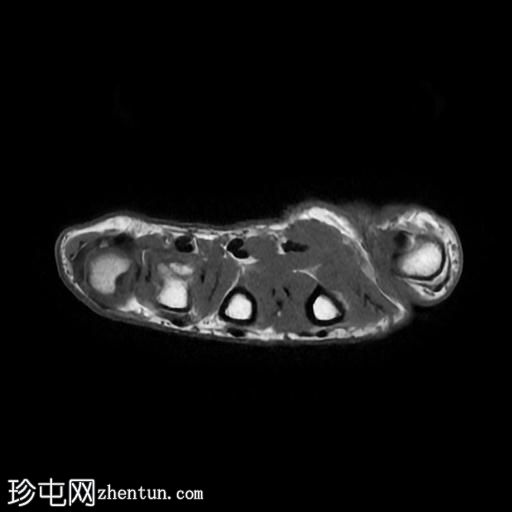

轴位

T2加权像

5.jpg